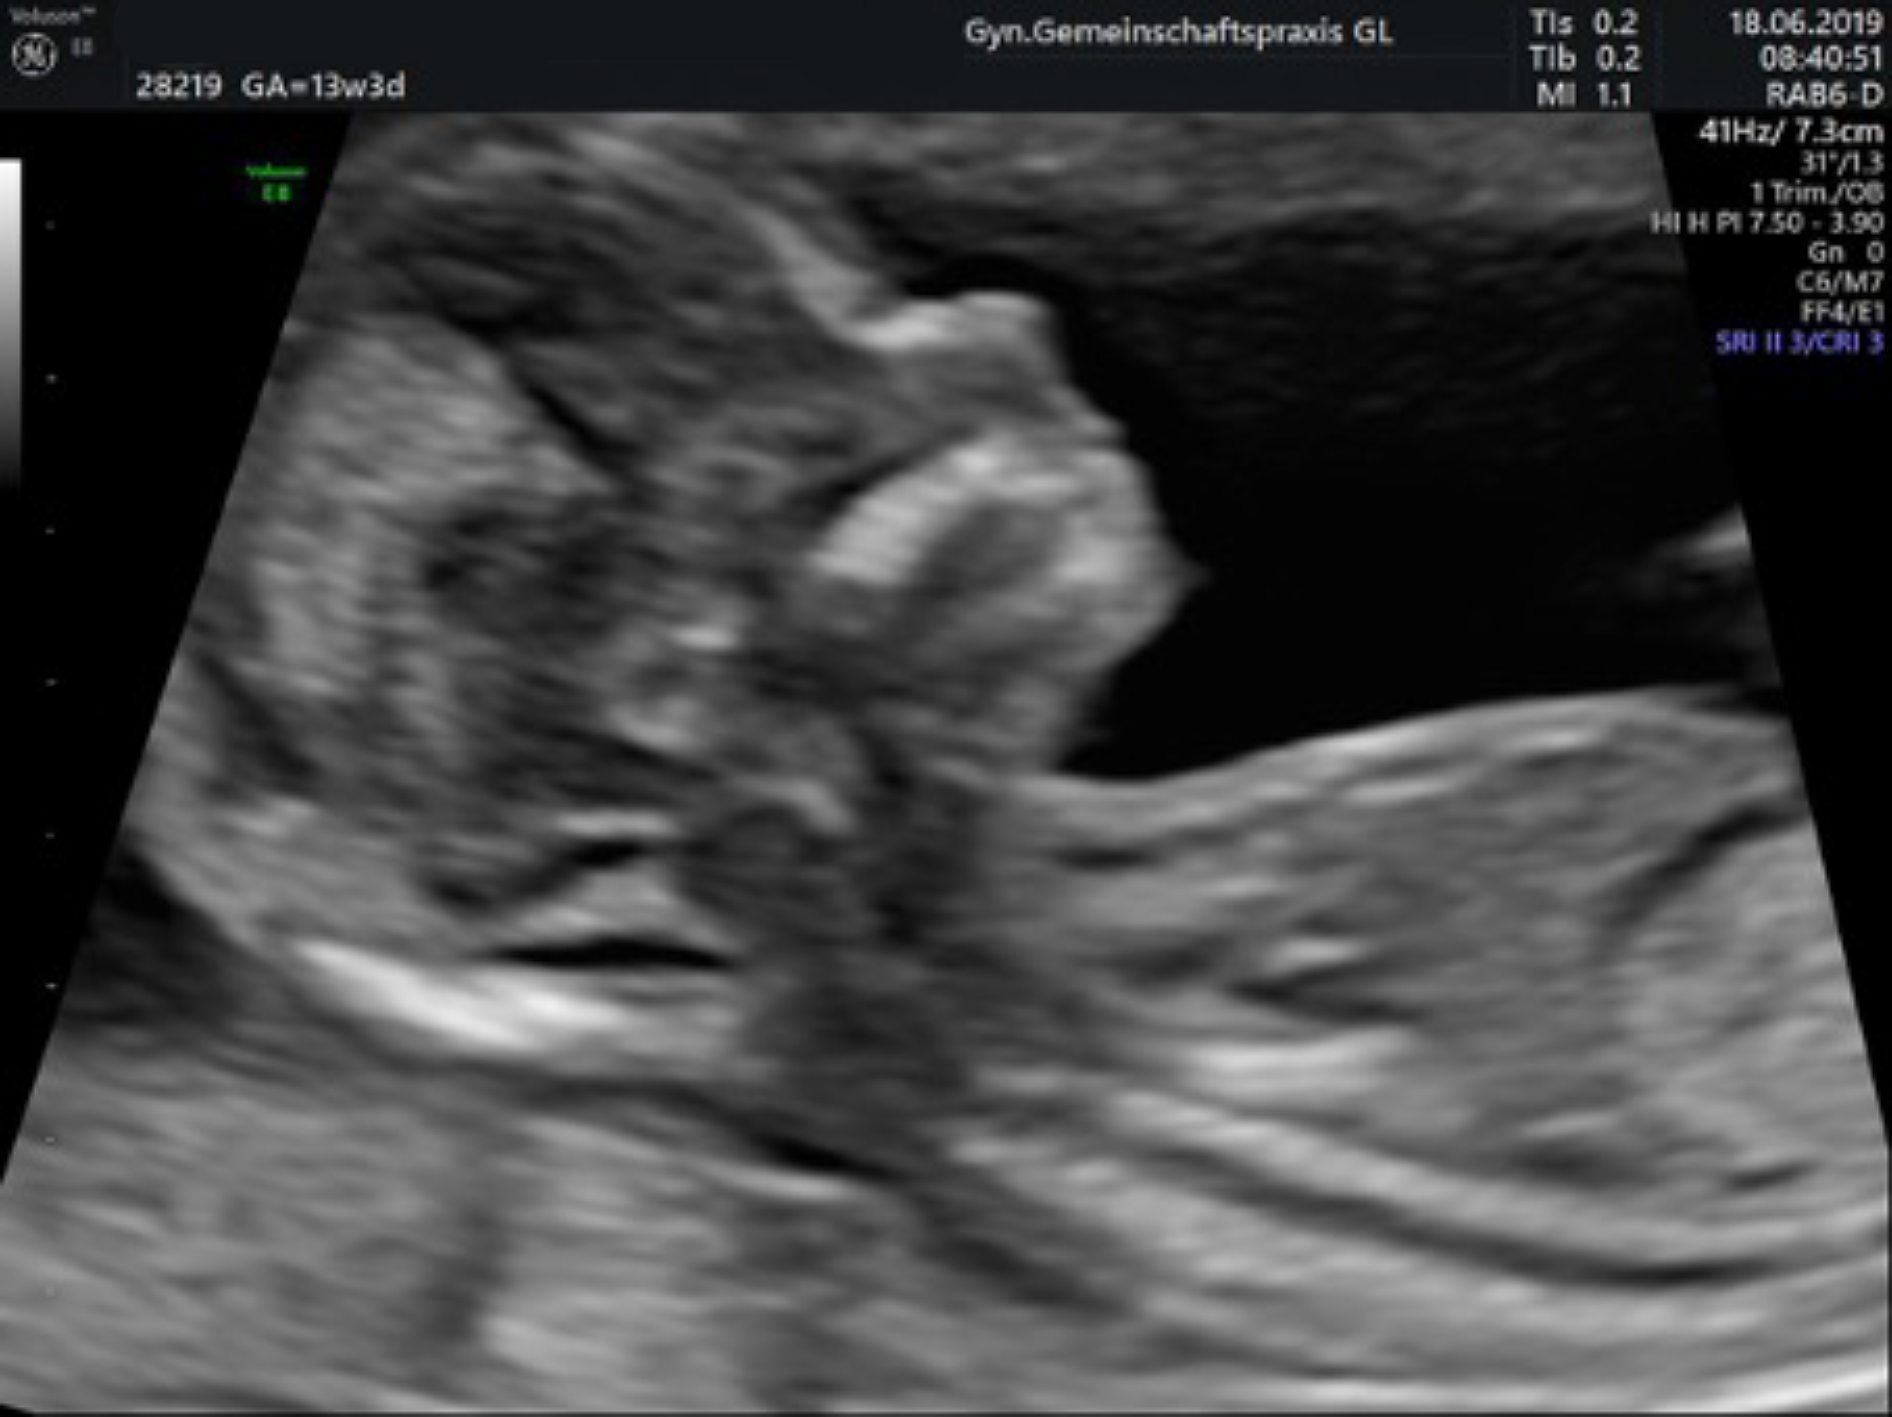

Ersttrimesterscreening mit individueller Risikoberechnung

(auch Nackentransparenzmessung/frühe Organdiagnostik genannt)

Zwischen der 12. und 14. Schwangerschaftswoche lagern die Kinder Flüssigkeit im Bereich des Nackens ein. Bei manchen Kindern ist dies verstärkt der Fall und kann dann zusammen mit Veränderungen bestimmter Blutwerte der Mutter einen Hinweis auf eine Chormosomenstörung (z. B. ein Down-Syndrom) geben.

In sehr großen Studien an über 100.000 Schwangerschaften wurden diese Messwerte mit der Risikoerhöhung für einen Chromosomenfehler des Kindes überprüft, die Vorhersagegenauigkeit ist deutlich besser, als die Abschätzung über das Alter der Mutter (bis ca 90%).

Zusammen mit einem ausführlichen Ultraschall (frühe Organdiagnostik) incl. des kindlichen Nasenbeins, der intakten Funktion einer Herzklappe und dem Blutfluss zwischen Mutter und Kind wird die Zuverlässigkeit der Risikoberechnung noch genauer und kann dann auch auf andere Fehlbildungen, z. B. einen Herzfehler oder einen offenen Rücken, hinweisen.